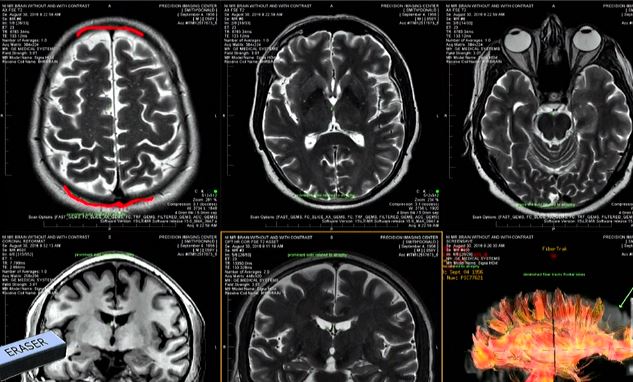

Dr Geoff Colino met with #DonaldSmith April 6 at the jail. He's a neurologist who conducted a history and physical & analyzed Smith's MRI brain scans @FCN2go

#DonaldSmith MRI scans being discussed @FCN2go